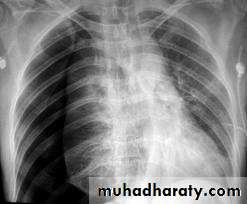

• CXR: Spontaneous pneumothorax is usually confirmed by chest x-ray ..

1. Expiratory films are better at demarcating the pneumothorax pleural line.2. Films should be done with patient standing, not supine.

• Supplemental oxygen: increases the rate of pneumothorax absorption.- Cautious observation in the asymptomatic patient with <15% pneumothorax can be done but requires close daily outpatient monitoring.